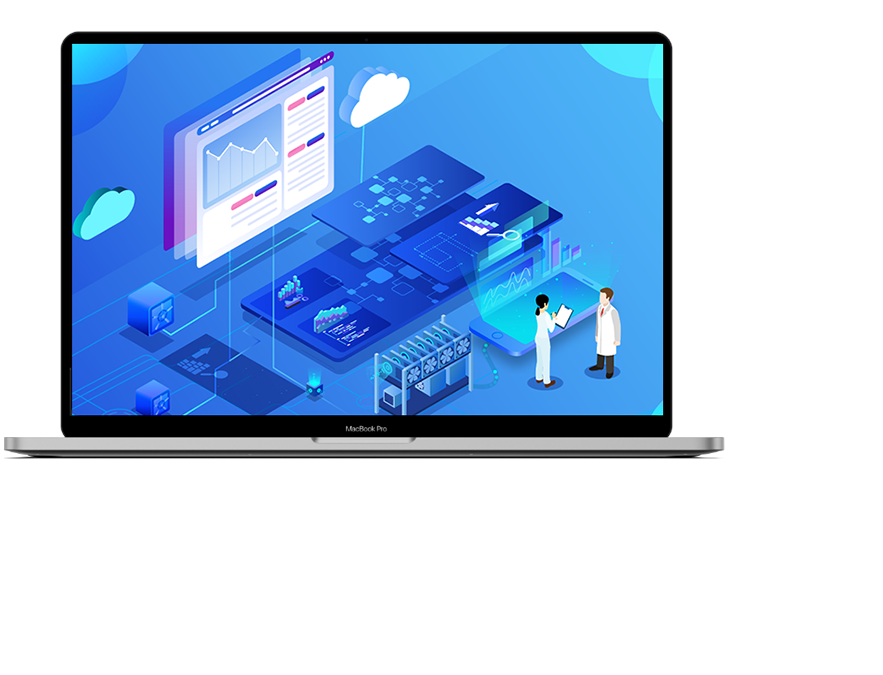

志御科技致力于成為全球肝

腦醫療AI領域的創新引領者

上海志御軟件信息有限公司(簡稱:志御科技)是中國領先的高科技醫療AI創新企業,創始團隊由知名醫學影像科學家隊伍及世界500強企業資深管理和營銷精英組成。公司致力于成為全球肝、腦醫學影像AI分析、AI輔助診斷以及AI遠程醫療的創新引領者,打造肝、腦醫療AI第一品牌。